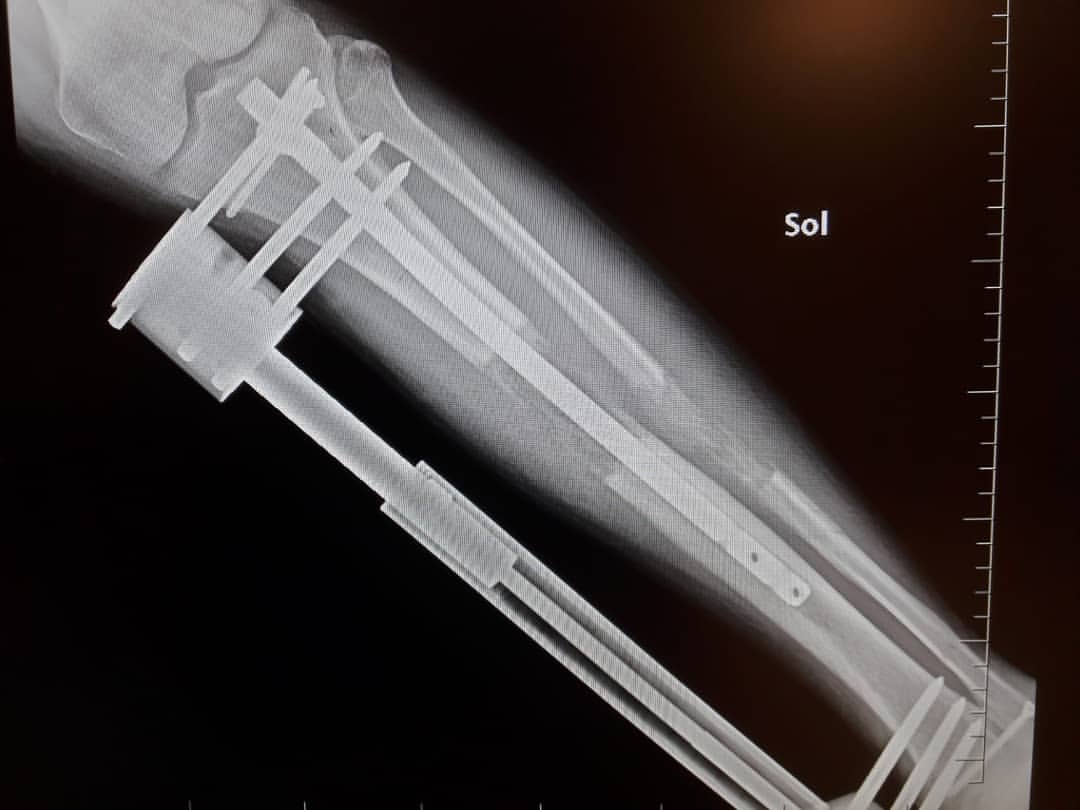

In Most Cases, The Tibia (Lower Leg) Is Operated, But There Are Also Cases Where The Femur (Upper Leg) Or Both The Femur And The Tibia Are Operated.

The leg is fixed using special methods and devices (external or internal fixing devices). It is a highly invasive surgery and not free of risks. Limb lengthening surgery in turkey is mostly done by lengthening the upper and lower leg bones, known as the femur and tibia.

Leg lengthening surgery with intramedullary lengthening nail fitbone ® saa. There are several reasons that turkey is a favorable country for leg lengthening procedures. Your surgery will be done in acıbadem hospital one of turkey’s and europe’s best hospitals.

Leg lengthening surgery is available in several countries worldwide. In some cases turkey can provide treatment only using an intramedullary rod without any external apparatus. In limb lengthening surgery turkey;